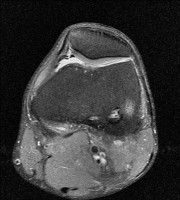

무릎 mri 간단히 봐주실 수 있으시나요 ㅠㅠ

안녕하세요 8년전 십자인대 수술하고 최근 무리한 운동에 무릎 불편감이 생겨서

mri 찍었습니다.

진단결과는 첫 찍은 병원에서 활액막염 이라는 진단을 받았습니다. 혹시 봐주실 수 있으실까요?

• 3번 째 사진

• 안녕하세요. 강성주 의사입니다.

올라온 MRI가 단편적이라서 정확한 진단에 어려움이 있지만 십자인대에는 큰 이상이 있지는 않은것 같으며, 무릎관절내 물이 있는 것으로 보아 활액막염의 진단이 맞을 것 같습니다.

하지만 단편적인 영상이기 때문에 촬영병원에서 정확한 판독지 등을 받으시는 것이 좋겠습니다.